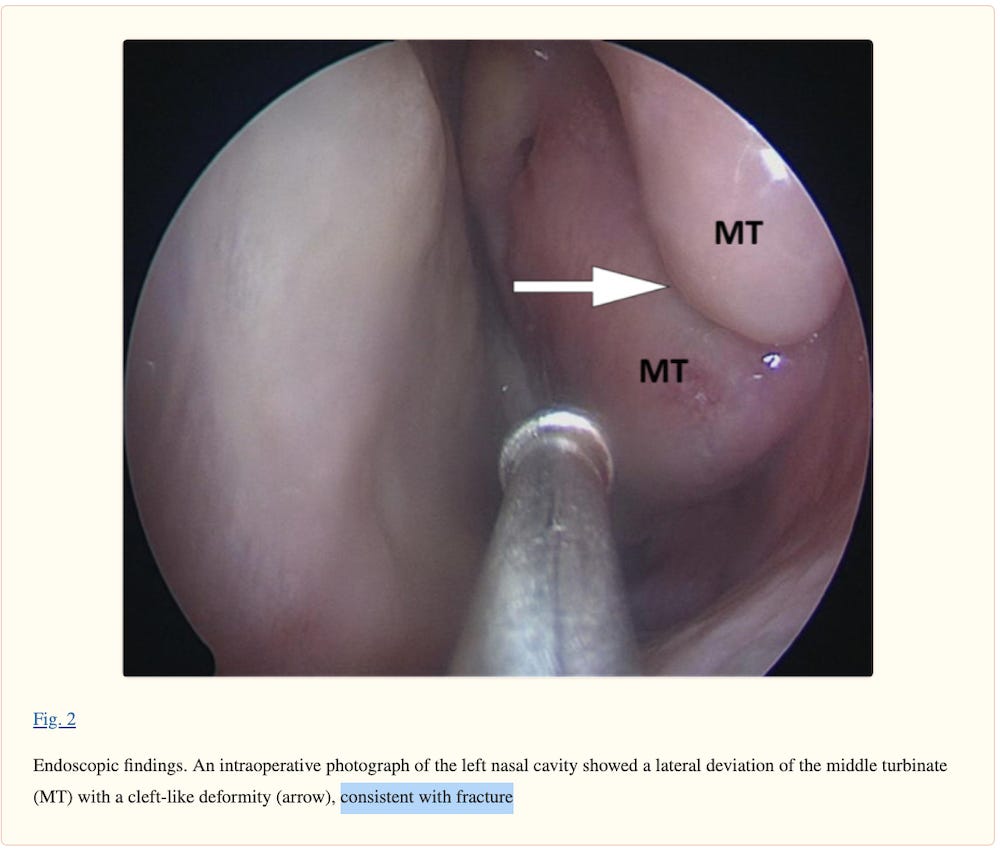

A healthy male in his 40s presented with a 3-month history of frontal headache and post-nasal drip, which did not improve with oral antibiotics. One month prior to the onset of the symptoms, he underwent a nasopharyngeal swab testing for SARS-CoV-2 (which yielded a negative result) for a history of malaise and cough. The patient claimed that the swab insertion into the nasal cavity was particularly painful on the left side. He denied any history of facial trauma, nasal surgery, or chronic sinusitis, and his medical history was unremarkable.

Sinus computed tomography (CT) scan showed a lateral deviation of the left middle nasal turbinate. The patient was diagnosed with ethmoid silent sinus syndrome. He was admitted to the hospital for endoscopic surgical repair. Intraoperative endoscopy revealed that the left middle turbinate was laterally deviated, with an umbilication-like deformity in its middle third. The findings were consistent with a fracture, and it was likely related to the nasopharyngeal swab testing performed 1 month before the onset of symptoms.